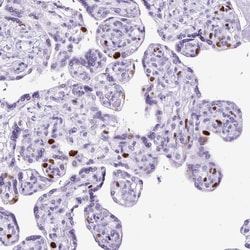

Invitrogen™ RACGAP1 Polyclonal Antibody

| Immunohistochemistry (Paraffin), Western Blot, Immunocytochemistry | |